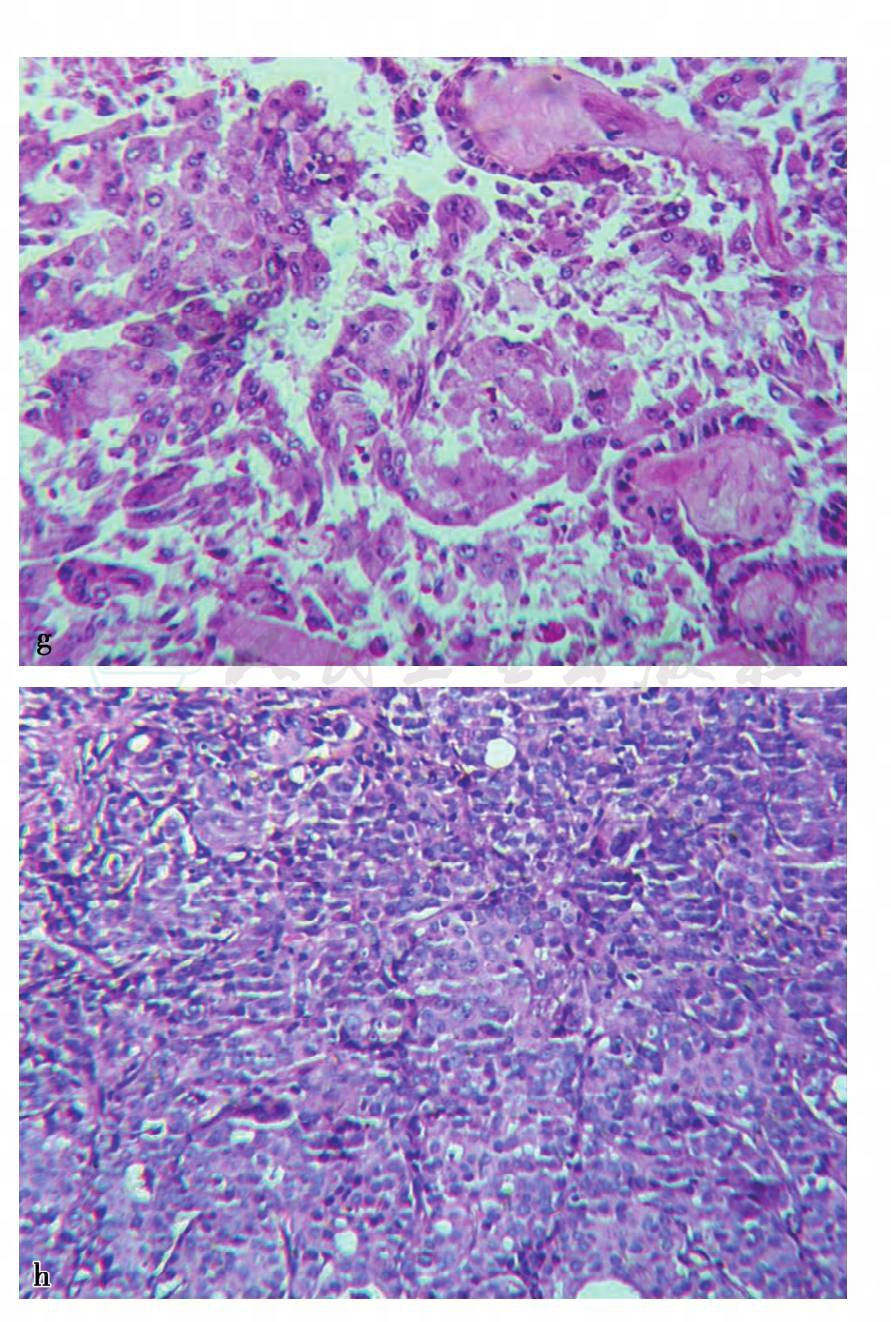

图2 g、h,病理结果为浸润性癌(见文后彩图)

诊断:病例2,浸润性癌,局部见脉管内癌栓

图19 c,病理示镜下可见导管上皮增生呈乳头状